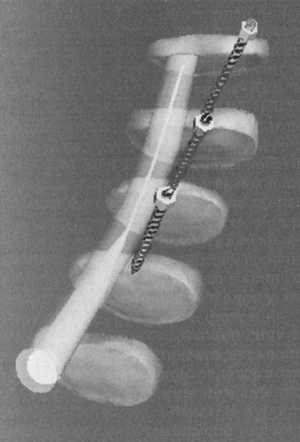

На рис. 7.8 приведена боковая костная проекция без контуров тела нашей модификации

входных точек и углов наклона транспедикулярных шурупов. На рис. 7.9 приведено

то же положение шурупов в косой проекции. На рис. 7.10 убраны контуры позвонков

(красные - межпозвонковые диски, розовый - дуральный мешок). Шурупы не ввинчены

в тела, видно их исходное положение. На рис. 7.11 в боковой проекции видно насколько

латерально от дурального мешка располагаются транспедикулярные шурупы. На рис.

7.12 тоже визуализируется в косой проекции. На рис. 7.13 видны костные структуры,

шурупы ввинчены в тела позвонков. На рис. 7.14 представлен полупрозрачный вид

всех структур. Видно положение шурупов в телах позвонков их соотношение с дуральным

мешком. На рис. 7.15 приведен полупрозрачный переднебоковой вид позвоночника,

видно положение шурупов в телах позвонков. На рис. 7.16 приведен боковой полупрозрачный

вид. Видно точное прохождение шурупов через корни дуг в тела позвонков.